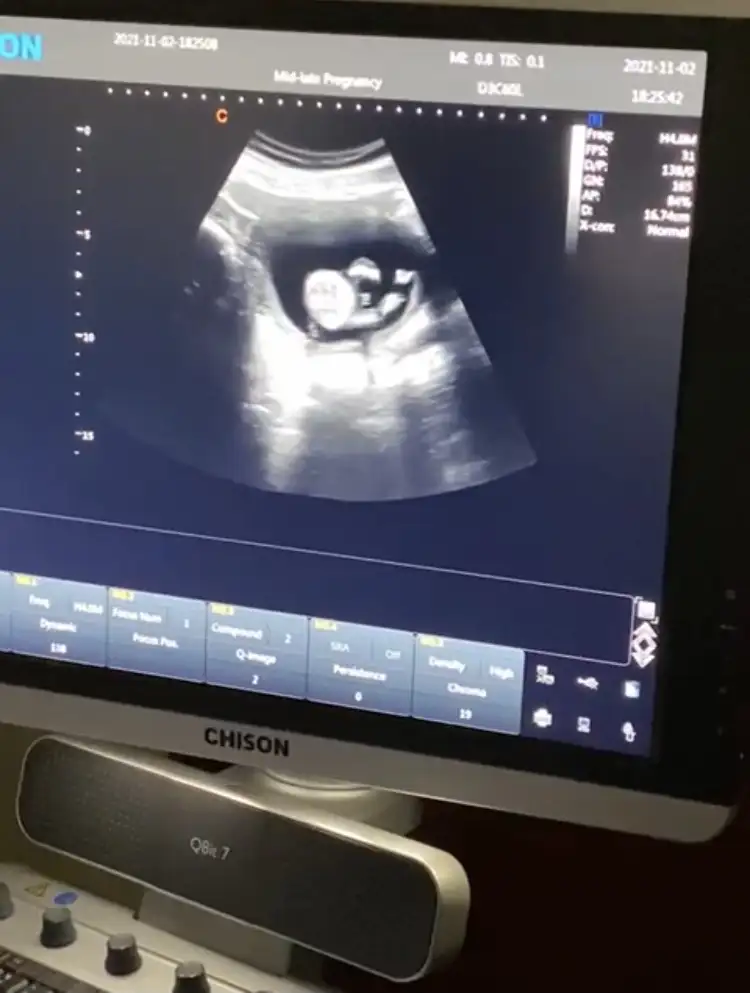

Suan kac haftalik acaba? Tam belli olmuyor malesef

11Suan kac haftalik acaba? Tam belli olmuyor malesef